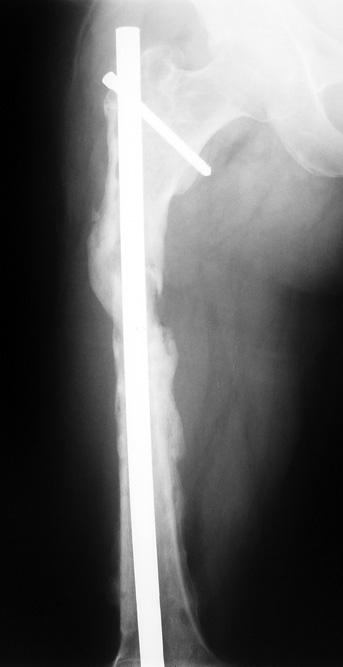

Appropriate radical debridement necessitates excision of all necrotic bone and soft tissues, and frequently causes instability at the involved extremity. The remaining bone and soft tissue defect has to be fixed and reconstructed. The distraction osteogenesis method of Ilizarov is used successfully for achievement of union, correction of the deformity, elimination of limb length inequality and reconstruction of segmental bone defects.

The duration of external fixation (external fixation index) depends on the amount of distraction required, and the extremity is prone to complications during this period. After the distraction phase is completed, the external fixator remains in place during the consolidation phase, which lasts twice as long as the distraction phase; but this period is hardly tolerated. If the external fixator is removed before sufficient consolidation is achieved, fractures, deformity and shortness will be the result. In our department, ‘lenghthening over nail’ method is used in order to decrease the external fixation index and increase patient comfort and activity level. In this method, the intramedullary nail is statically locked after the completion of the distraction phase, and external fixator is removed. The extremity is stabilized by the intramedullary nail during consolidation phase. In this way, complications due to long external fixation index or early removal of the external fixator are avoided.

Case 1